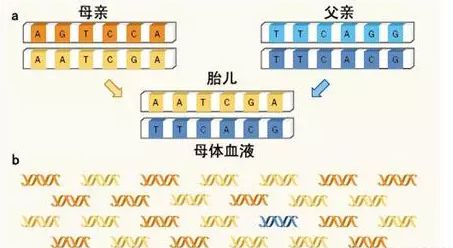

西安无创DNA亲子鉴定收费标准及流程? 近些年,无创产前亲子鉴定以其安全系数、便利性而遭受很多沒有孕妈妈的关心,针对西安想做亲子鉴定的被告方来讲,...

西安孕期无创亲子鉴定最早多久能拿到结果?需要多少钱?现在怀孕期间也是可以做胎儿亲子鉴定了,即无创亲子鉴定。整个检测周期在7-10个工作日。收费在7000-8500左右...